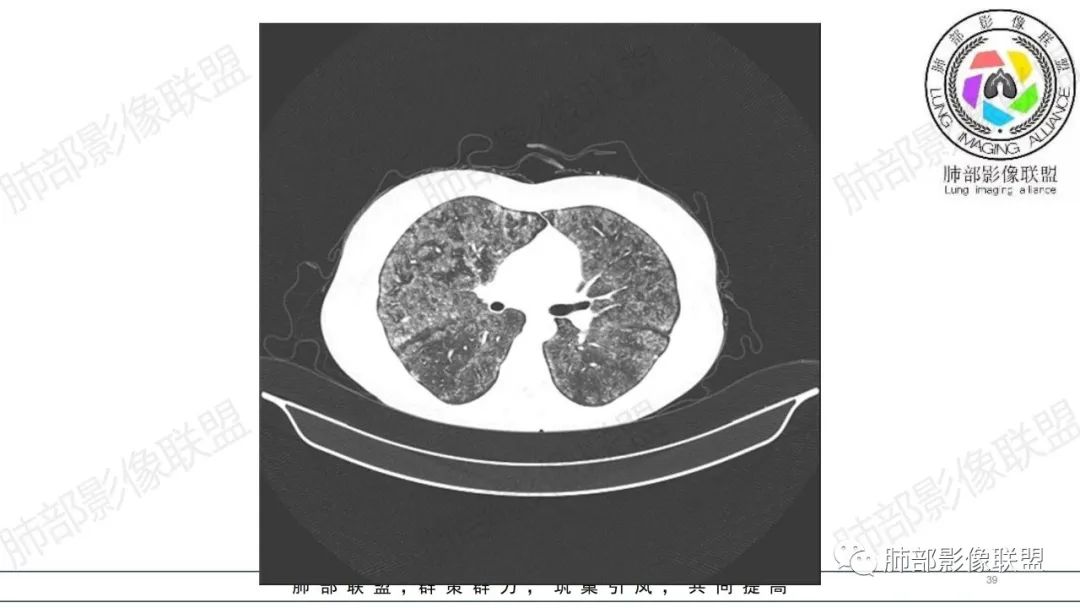

34岁女性患者,“哮喘”病史30年,近期有可疑刺激性气体吸入史;因乏力半年,咳嗽、憋气、发热4天就诊;6.1CT提示双肺广泛毛玻璃影及粟粒样结节,胸膜下闲置及血管周闲置,可见树丫征,部分小叶间隔增厚。考虑:1.过敏性肺泡炎,有可疑刺激气体接触史,胸膜下闲置,广泛毛玻璃影,地图样分布,粟粒结节边界模糊,支持过敏性肺泡炎,但糖皮激素治疗效果不佳,且动态复查血常规血红蛋白进行性降低,过敏性肺泡炎 不符合;2.肺含铁血黄素沉积症:患者30“哮喘”病史,可能为肺含铁症状,肺部CT提示双肺弥漫毛玻璃影及粟粒结节影,中下肺明显,肺底部分小叶间隔增厚,近期咳嗽、憋气、发热,血常规血红蛋白进行性下降,考虑肺含铁急性期症状,但临床无咯血症状,肺含铁不典型。综合考虑:肺含铁血黄素沉积症>过敏性肺泡炎。

年轻女性 ,急性喘息发热,肺部影像弥漫磨玻璃密度,部分细小腺泡结节,胸膜下黑线显示,短期复查,病变密度增高,下肺明显,血管周围肺组织累及较少、且逐渐成小叶间隔分布。考虑弥漫肺泡内病变,并经淋巴道转移,下肺比上肺明显,多为免疫细胞功能下肺较强。1.过敏性肺泡炎,有相关病史,三层密度特点、头尾测分布,符合。2 肺泡微石症,多有钙化,且缓慢起病,病程不太符合,放待排。3 吸入相关肺损伤,有病史,疾病演变过程也符合渗出-肉芽肿改变,建议详细询问病史。4 感染性病变,结核?病变气道分布为主,如此弥漫且没有树丫不符合。5.巨细胞病毒,可以磨玻璃 结节 改变,没有免疫缺陷病史。最后考虑吸入所致 1过敏性肺泡炎、吸入性肺损伤 鉴别肺泡微石症。

肺内气腔磨玻璃结节,肝脾肿大,治疗后间质改变,弥漫大B可能